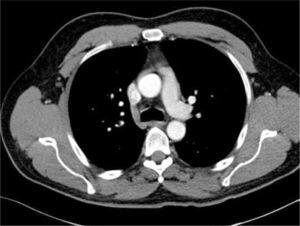

TOMOGRAFÍA COMPUTARIZADA AXIAL DEL TÓRAX

Se muestra cómo los vasos sanguíneos mamarios, pleura medial a la derecha, vena cava superior, aorta ascendente, y vena ácigos son todas similares en el primer y segundo plano. Los catéteres en cada una de estas diferentes estructuras no se distinguen claramente en el plano de la imagen (Radiografía de tórax).

Ante esta situación, los catéteres son fácilmente reconocidos como mal colocados y generalmente no se necesita el consejo de un especialista antes de su revisión, uso o retiro. Los catéteres pueden estar en una posición obviamente incorrecta fuera de la vena o puede parecer que siguen una ruta normal aproximada a través de la radiografía torácica, pero no están correctamente colocados en la vena cava superior. Las imágenes de tomografía computarizada axial muestran que no se pueden distinguir un catéter en una imagen plana el espacio pleural derecho, los vasos mamarios internos derechos, el sistema ácigo, la aorta ascendente o el mediastino (Figura 8). La radiografía torácica sólo puede confirmar el paso del catéter central, plegamientos de éste o complicaciones de procedimiento.